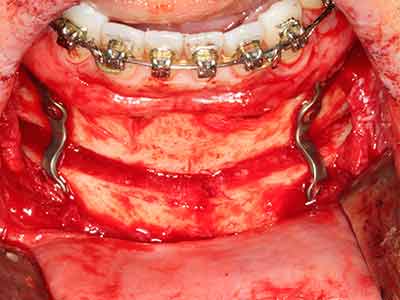

Bone tissue is not simply a mineral structure but also contains a substantial proportion of collagen fibres. This means it not only has good compressive strength but also a degree of flexibility, which can be taken advantage of when performing bone augmentations. In the classical expansion procedure using bone splitting, the atrophied alveolar ridge is split longitudinally and carefully expanded after reaching an adequate osteotomy depth (Fig. 13-16), ideally without substantial removal of the periosteum (Brugnami, Caiazzo et al. 2014, Stricker, Fleiner et al. 2014). Screw and plate systems with increasing expansion distance have proven effective in separating the two bone lamellae while remaining below the fracture threshold. In general, residual bone widths of at least 3–4 mm are required (Chiapasco, Zaniboni et al. 2006) to guarantee adequate flexibility and sufficient bone coverage of the future implants. If necessary, a vertical relief osteotomy on one or both sides can improve flexibility. A combination with additional augmentation techniques, particularly on the buccal side, has been described as an alternative to the classical technique.

The splitting procedure is particularly atraumatic and there is no significant loss of dimension when using piezosaws, and there are no significant differences between implants in split jaws and implants in an alveolar ridge without a bone deficit (Chiapasco, Zaniboni et al. 2006, Danza, Guidi et al. 2009). However, sufficient continuous irrigation is essential, particularly with locally restricted and deep splitting to prevent thermal stress in the apical osteotomy regions.

Fig. 13: Adequate irrigation with the 4-mm residual bone width is essential for this 52-year-old patient during the bone splitting.